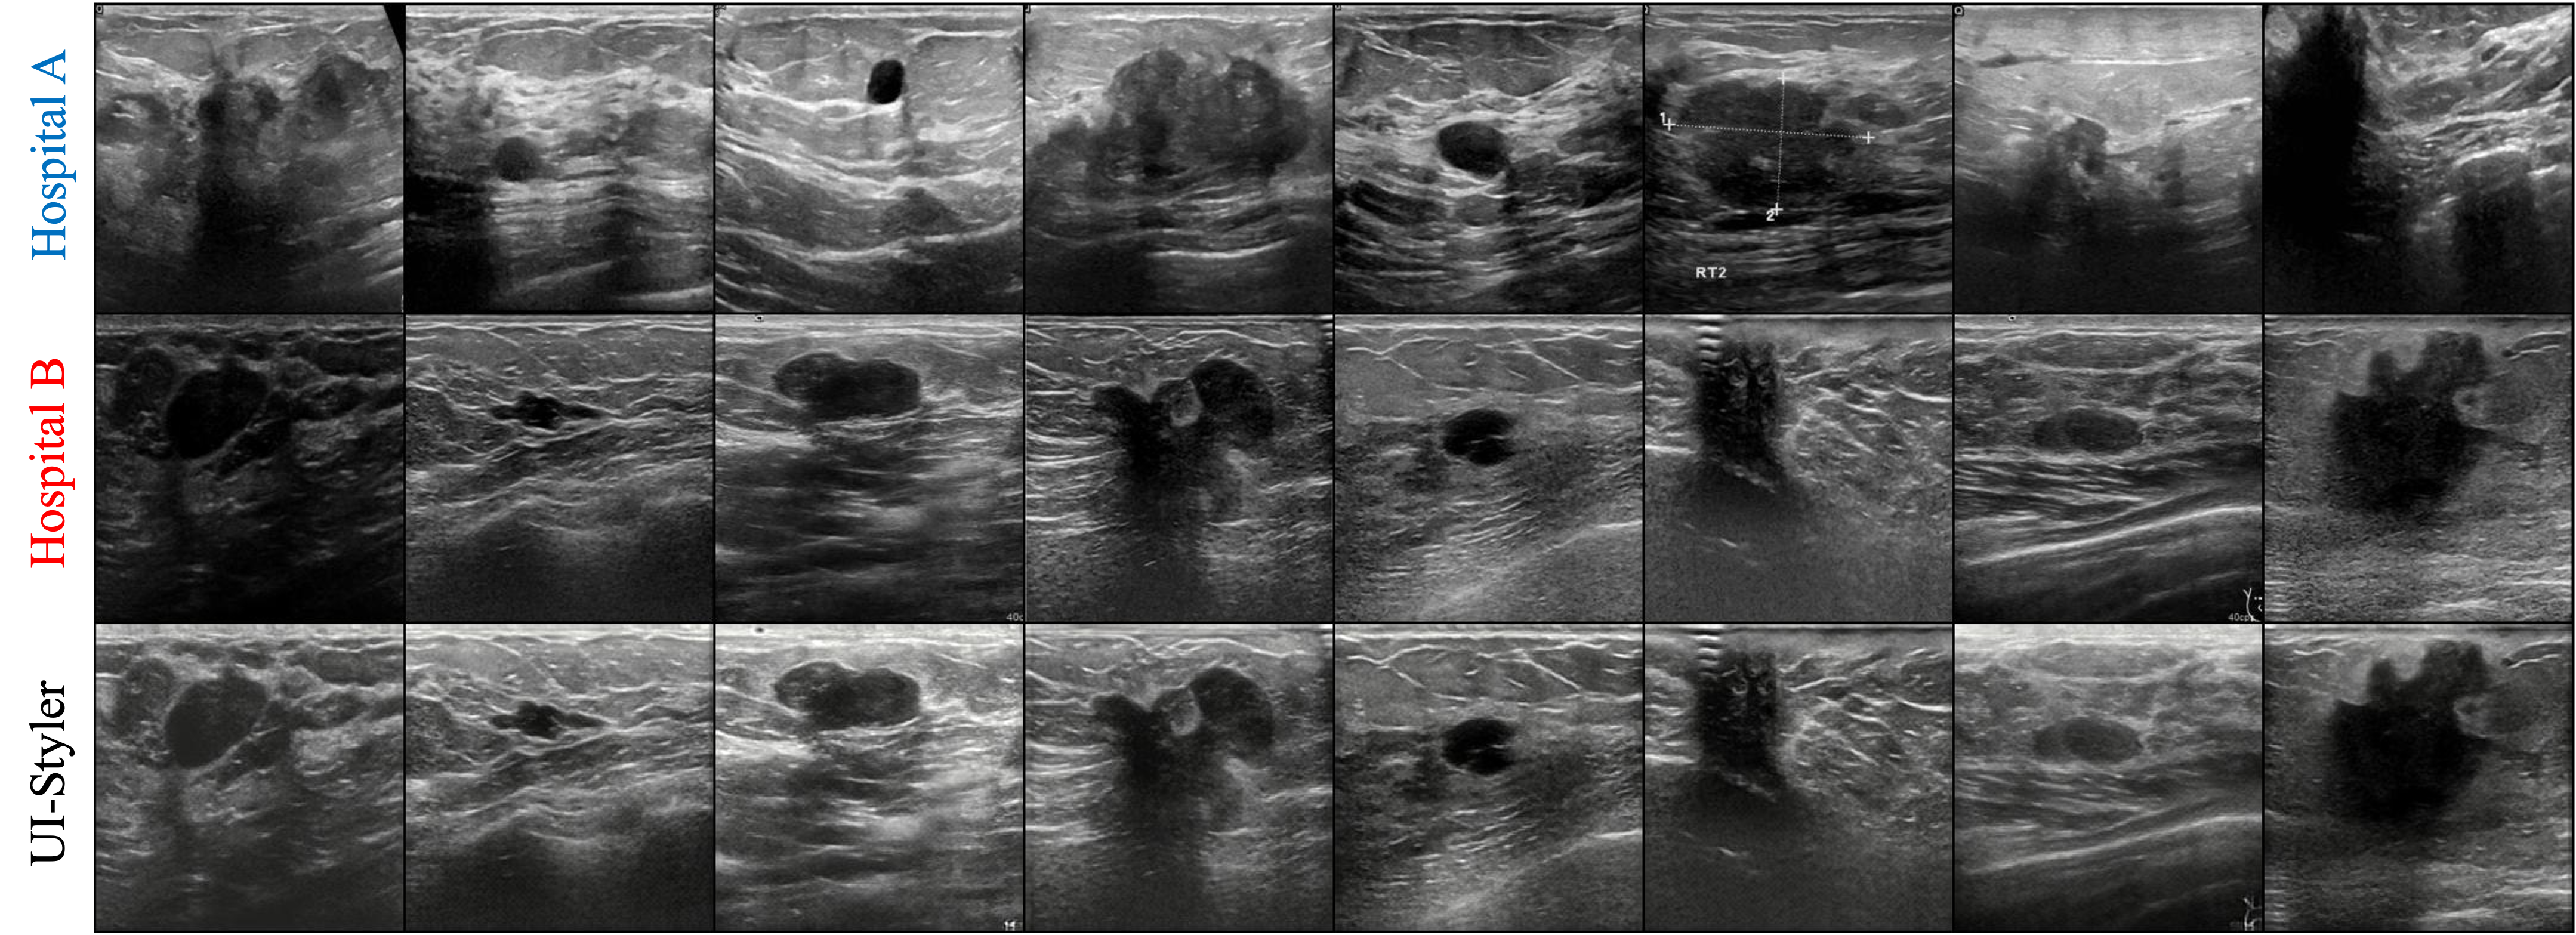

🖼️ Visual Results